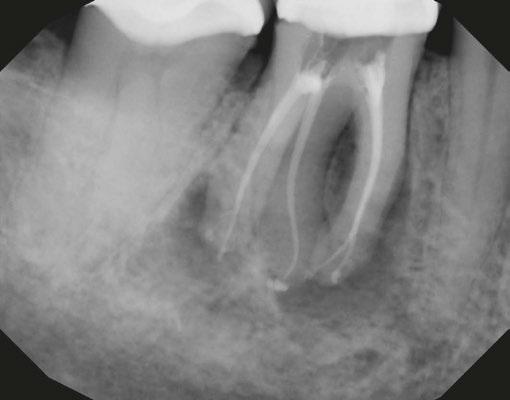

Case 2: Pre-op and diagnosis: A 52-year-old female presented with a chief complaint of pain to hot and cold. Pulpal sensitivity testing on tooth No. 31 revealed a lingering, aching response to thermal testing. A clinical exam revealed a small crack extending from the occlusal resin over the distal marginal ridge. Probing depths around No. 31 were all <3 mm. No. 31 was diagnosed symptomatic irreversible pulpitis with symptomatic apical periodontitis. A pre-op small FOV CBCT revealed No. 31 to have a C-shaped canal morphology. Two treatment options were discussed with the patient: 1) Tooth No. 31 non-surgical root canal therapy or 2) No. 31 extraction. The patient elected No. 31 non-surgical root canal therapy (NSRCT). Treatment: No. 31 NSRCT, the patient was anesthetized with 68 mg Lidocaine with 0.034 mg EPI via IAN and 68 mg Septocaine with 0.017 mg EPI via buccal Infiltration. Rubber dam isolation was utilized, and access was prepared. Due to the C-shaped canal morphology, only two canals could be identified. Prior to placement of the SoundSeal platform, a small amount of bonding agent was placed over the crack along the distal marginal ridge and distal portion of the pulp chamber. The SoundSeal platform was securely placed to create a vacuum seal. The two canals were negotiated to achieve patency by alternating rotary instrumentation and the GentleWave CleanFlow Procedure Instrument for 30-40 seconds to thoroughly debride the internal anatomy. The mesial canal was instrumented to a Master Apical File of 20/.04, while the distal canal to a 25/.04 Master Apical File. Due to the larger and more irregular canal morphology of the distal canal, various-sized gutta-percha cones were used to gauge the size to be used for obturation. The mesial canal was obturated with a Sealer-based obturation method with High Flow BC Sealer and a single 20/.04 master cone. The distal canal was obturated with High Flow BC Sealer and Warm Vertical Compaction. With the aid of the GentleWave and the CleanFlow Procedure Instrument, the C-Shaped canal anatomy was more deeply cleaned, pulp tissue more thoroughly removed, and this case was completed in a single visit which would have been much more difficult to accomplish with traditional endodontic therapy.

10 Endodontic Practice US Volume 17 Number 1 COVER STORY